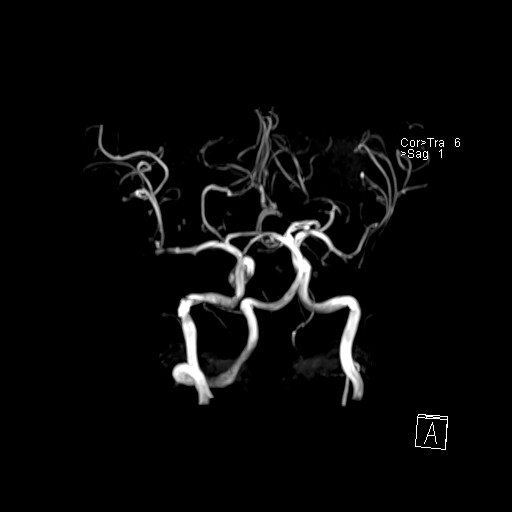

239716 - VILLANUEVA, WILLIAM A. - Number 1 |

|

239716 - VILLANUEVA, WILLIAM A. - Number 1 |